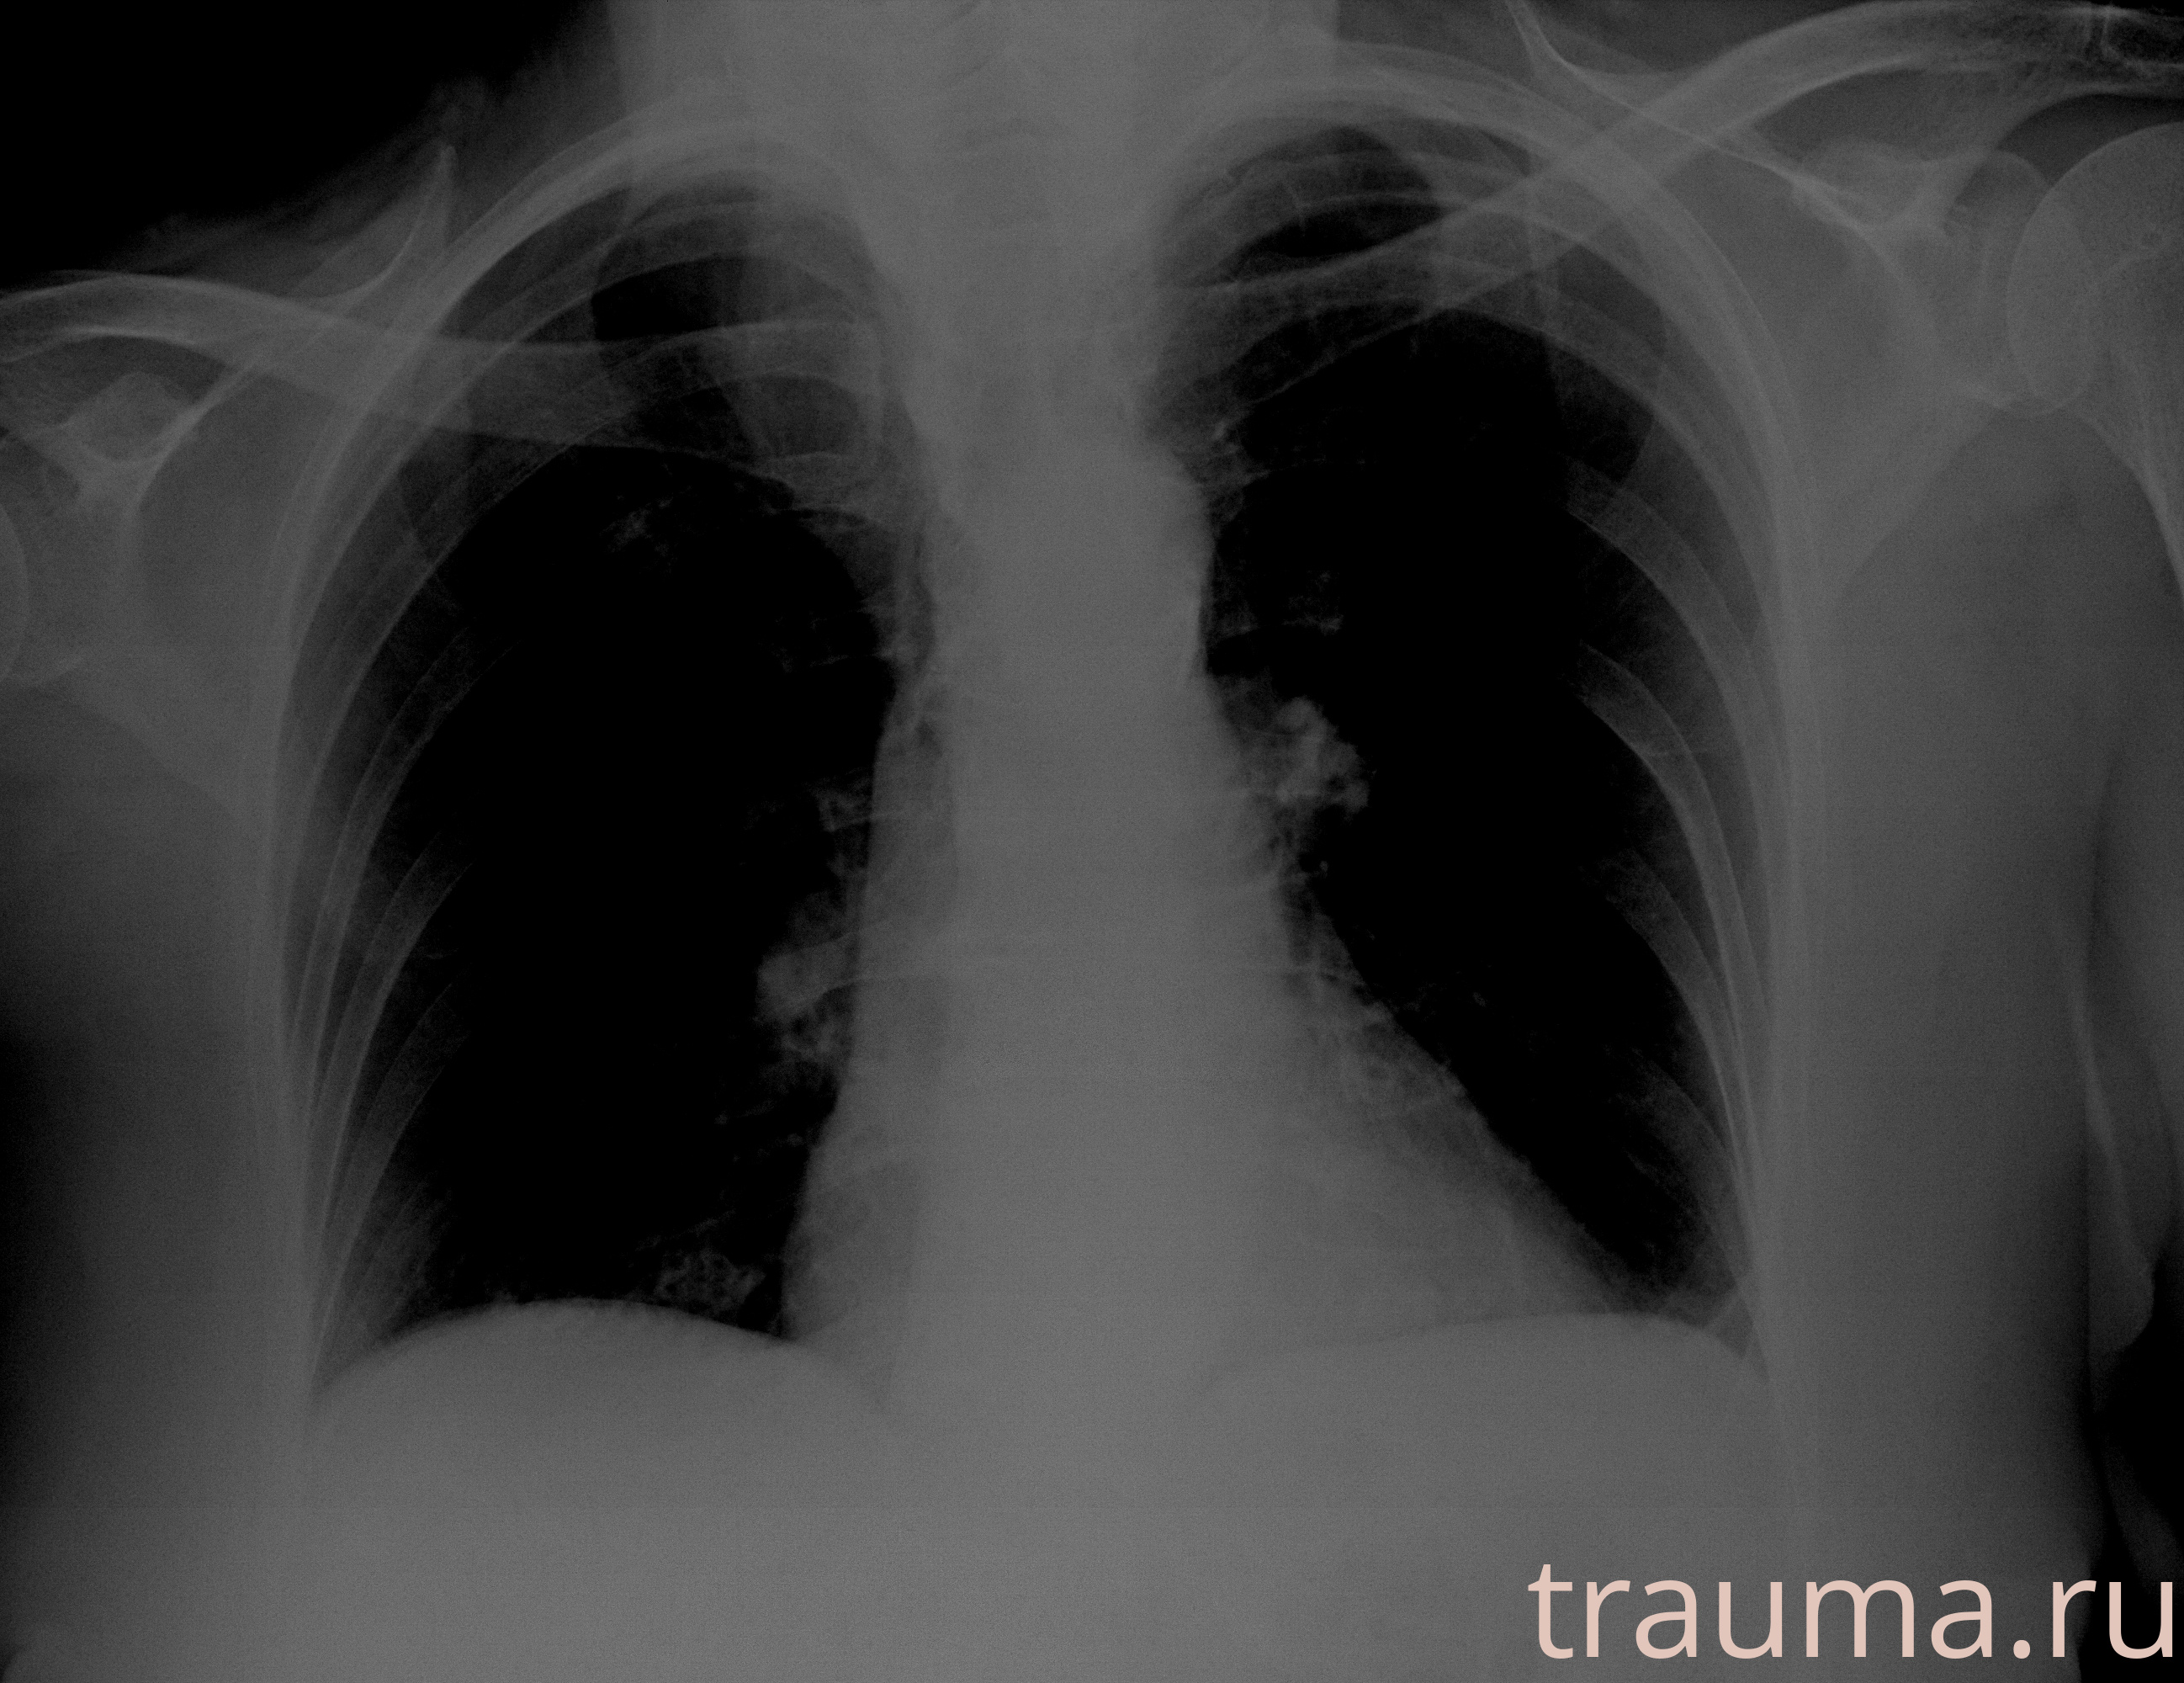

Рентгенограммы

Рентген на дому: по вашему адресу приезжает врач-рентгенолог, травматолог-ортопед с мобильным рентгеновским аппаратом, проводит диагностику травмы или заболевания, делает необходимые рентгенограммы, дает рекомендации по дальнейшему лечению. Получить качественные снимки в домашних условиях возможно благодаря уникальной методике, разработанной МосРентген Центром для института  Склифосовского

при переломе шейки бедра и пневмонии от компании МосРентген Центр - партнера Института имени Склифосовского